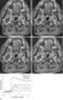

Necrotic lymphadenopathy

Lymphadenopathy or adenopathy is a disease of the lymph nodes, in which they are abnormal in size or consistency. Lymphadenopathy of an inflammatory type (the most common type) is lymphadenitis, producing swollen or enlarged lymph nodes. [Source: Wikipedia ]